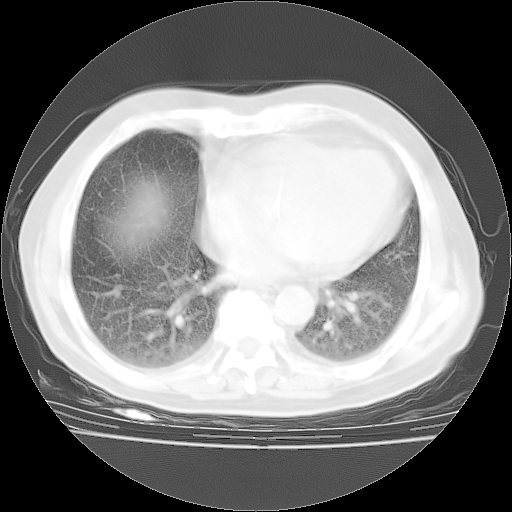

今天部分检查

轻微咳嗽,无痰,(体温正常时)R20次/分,P75次/分,双肺底、腋下可闻及少量捻发音。下肢轻度浮肿。

血常规:白细胞9.11×109/L,N0.92,L5.64,血小板39.2×109/L,HB148g/L,ESR2mm/H。

尿常规:潜血+

血生化:总蛋白69.71g/L,白蛋白38.40g/L,球蛋白31.31g/L,CRP27.9mg/L,尿素氮11.98mmol/L,肌酐106μmol/L,乳酸脱氢酶1099 U/L,肌酸激酶108U/L,CK-MB 61U/L。

腹部B超:胆囊壁增厚,肝、胆、胰、脾、肾无异常,肠系膜淋巴结、腹膜后淋巴结无增大。

ECG:右心室增大

心脏超声检查:无右心室增大。

增加治疗:异烟肼、利福平、乙胺丁醇,静滴左氧氟沙星、参麦注射液。甲强龙从80mg暂减为40mg。

强的松3月1日改为10mg qd,4月1日改为10mg qod。3月份以前的减量过程和环磷酰胺疗程需等明天查看记录(我岳父自己做的记录在他家里)。